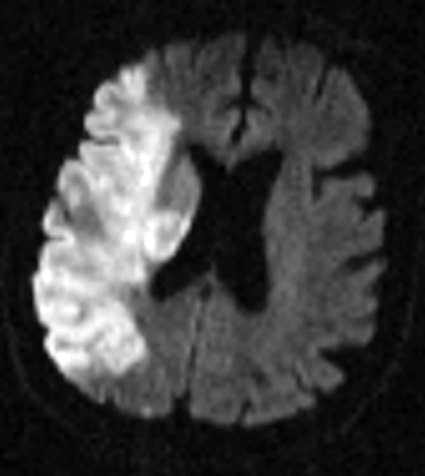

Figure 4: Vascular Malformations. The magnetic resonance image below shows a severe arteriovenous malformation (AVM) that was not discovered until the teenage years of a patient with worsening headaches, mental slowing, and new onset seizures. (Images courtesy of Dr. McMurtrey)